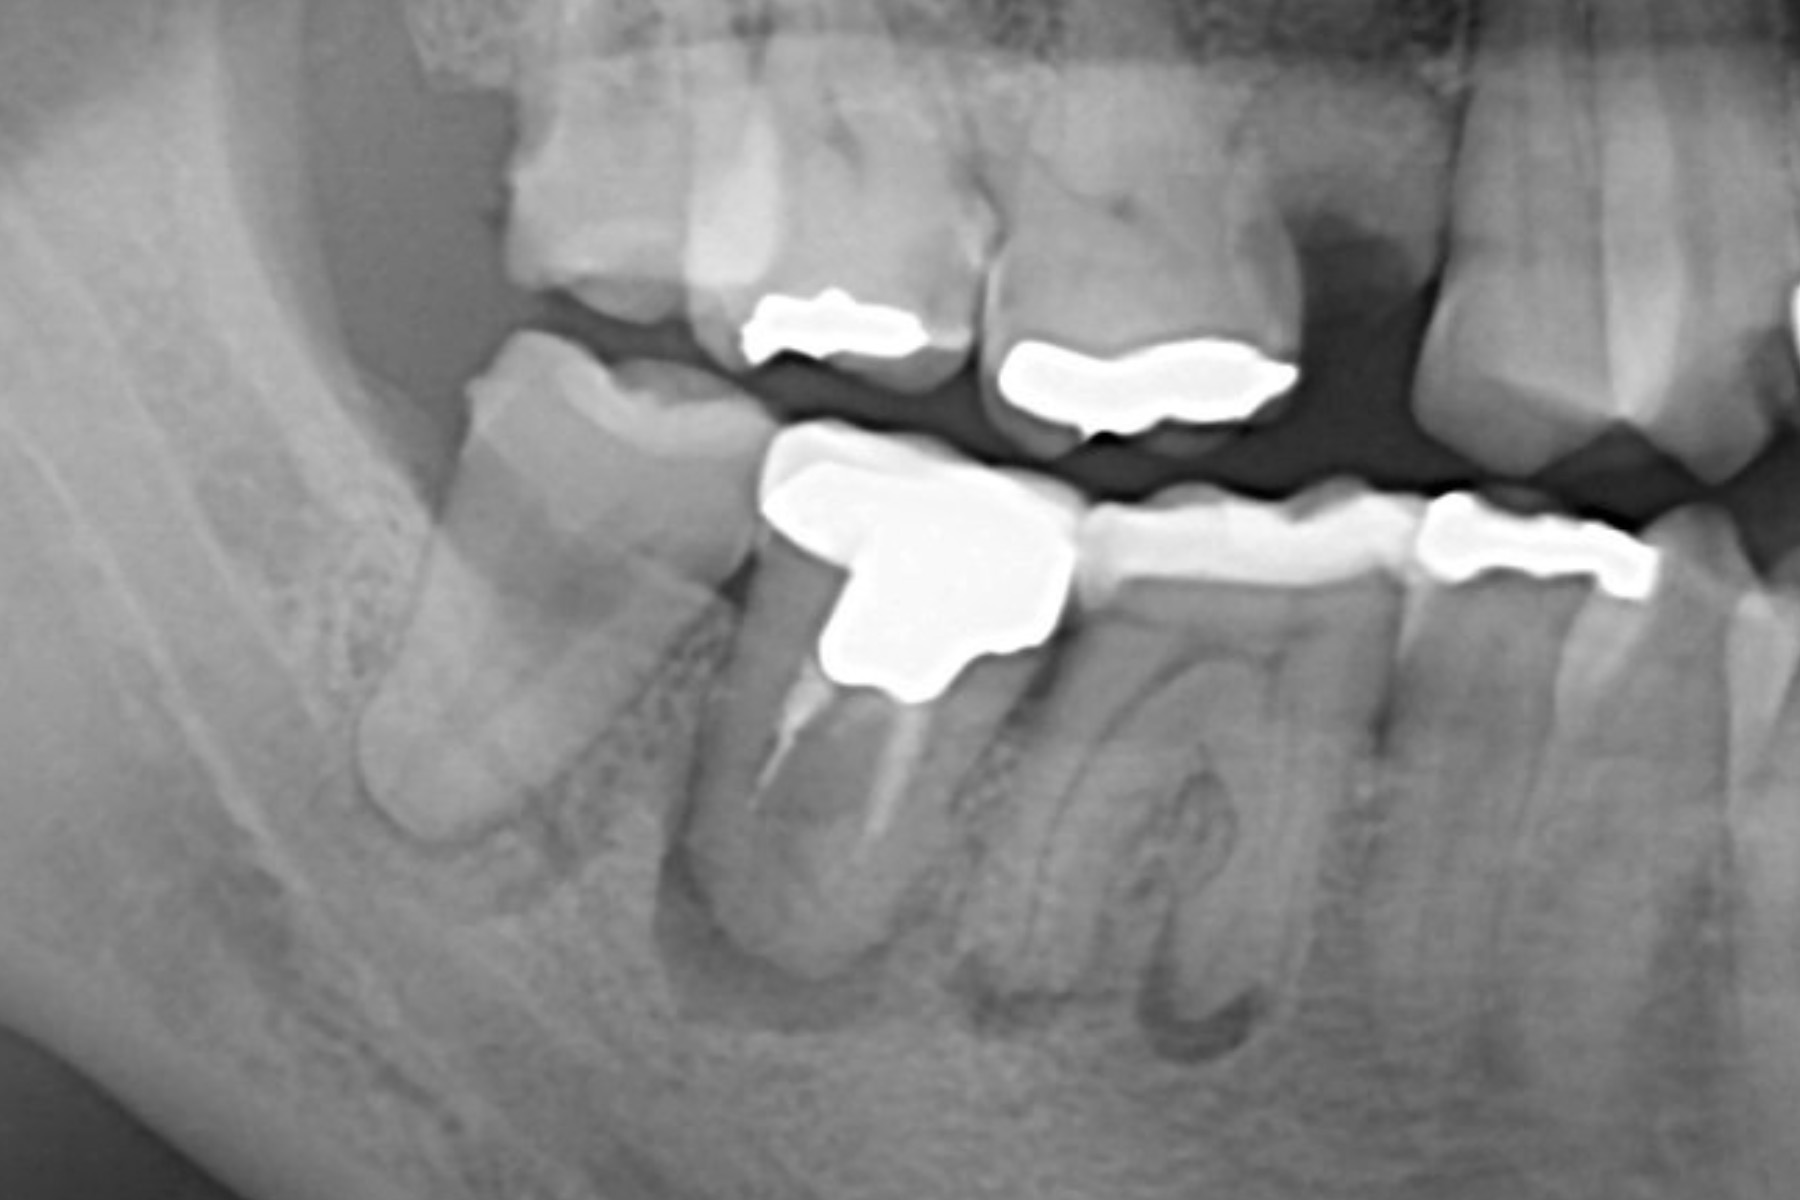

CASE22:親知らずの

症例

CASE22